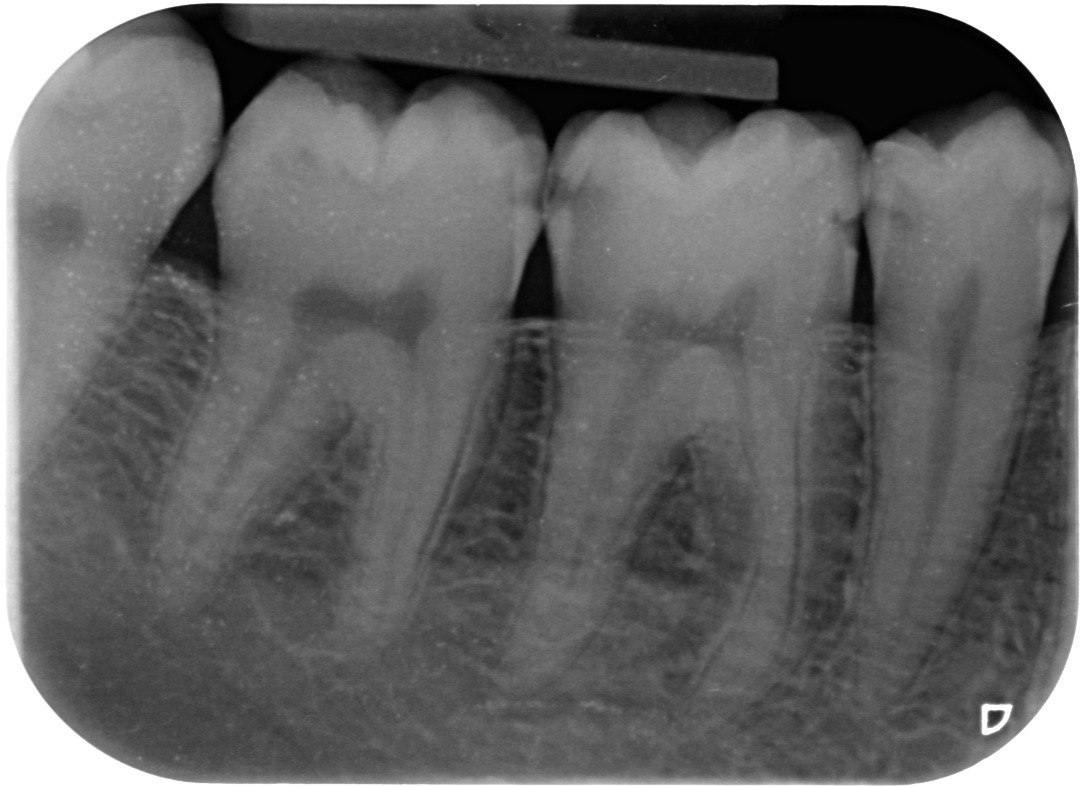

1. Which surfaces shows dental caries?